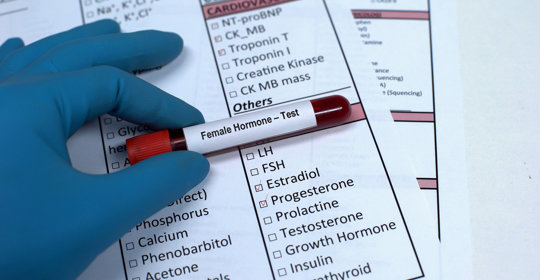

白帶拉絲:性周期、懷孕與健康相關

白帶拉絲:排卵期、懷孕、月經前後變化及處理方法